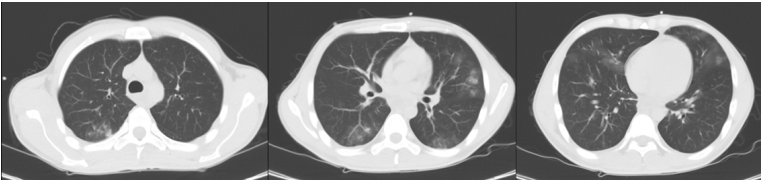

实际案例中,我们看到这一例ARDS患者,早期呈病毒性肺炎的磨玻璃样改变(图7),随着病情进展,11小时后氧合下降,胸部CT可见渗出增加、肺实变,予以气管插管,呼吸机辅助(图8);呼吸机支持2天后,胸部CT示实变进一步加重,呈现ARDS典型的“重力依赖”CT表现(图8)。这种情况可能就是呼吸机参数设置不当,加重了肺损伤。

图片

图7  患者入院早期胸部CT

图8  11小时后和2天后胸部CT